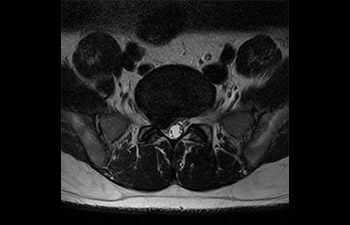

• Baanbrekende versnellingstechniek waarmee niet alleen sequenties versneld worden, maar uw gehele MRI-onderzoek. • Unieke implementatie waarmee 2D- en 3D-scans tot wel 50% sneller gemaakt kunnen worden met een nagenoeg gelijkwaardige beeldkwaliteit.1

• Kan gebruikt worden in alle anatomische contrasten en alle anatomieën.

met Compressed SENSE